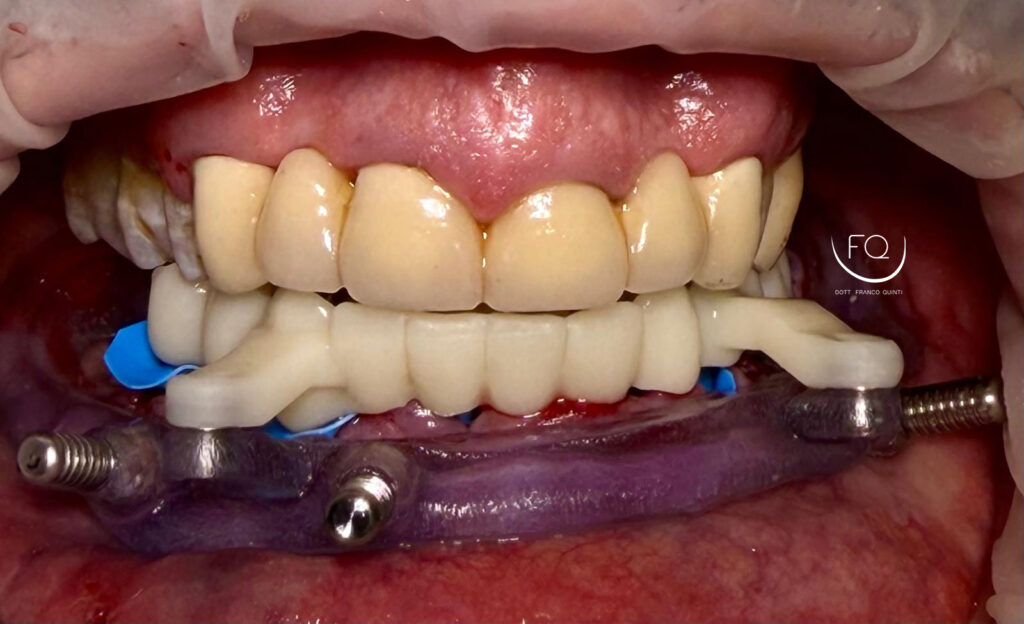

Dall’immagine iniziale è possibile apprezzare l’estrusione del gruppo incisivo inferiore il quale è stato corretta con la protesi provvisoria a carico immediato stampata in 3D.